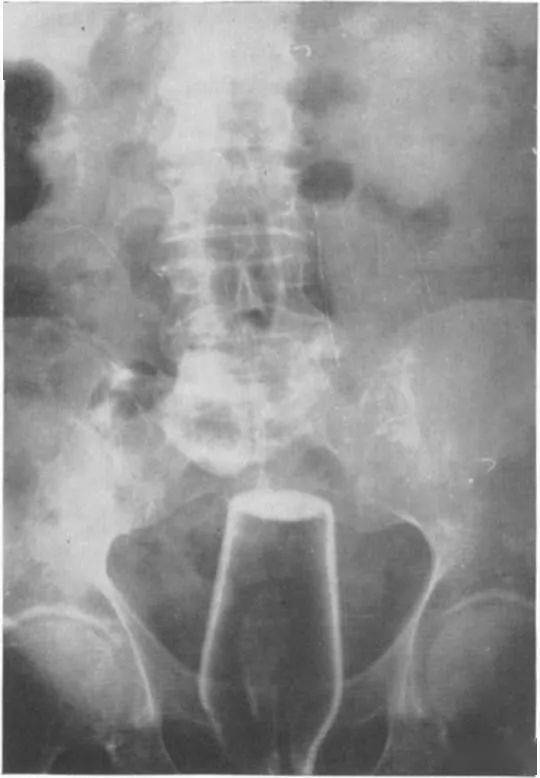

价值4.6万英镑的2磅 (约2斤重)黄金都塞进去了 , 如果大家对2斤重的黄金到底有多少没啥概念 ,这是海关人员拿出来的金子照片 。

据说 , 当时这名男子是因为 在机场走路姿势非常诡异 , 所以被工作人员拦下来进行了检查 , 这才发现了黄金 。Emmm…难以想象那是怎样尴尬的场景 。见多识广的网友都震惊了:“那么多金条塞进体内 , 他居然还能走 。 ”